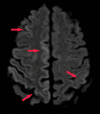

Neurodegenerative diseases are a devastating group of disorders that can be difficult to accurately diagnose. Although these disorders are difficult to manage owing to relatively limited treatment options, an early and correct diagnosis can help with managing symptoms and coping with the later stages of these disease processes. Both anatomic structural imaging and physiologic molecular imaging have evolved to a state in which these neurodegenerative processes can be identified relatively early with high accuracy. To determine the underlying disease, the radiologist should understand the different distributions and pathophysiologic processes involved. High-spatial-resolution MRI allows detection of subtle morphologic changes, as well as potential complications and alternate diagnoses, while molecular imaging allows visualization of altered function or abnormal increased or decreased concentration of disease-specific markers. These methodologies are complementary. Appropriate workup and interpretation of diagnostic studies require an integrated, multimodality, multidisciplinary approach. This article reviews the protocols and findings at MRI and nuclear medicine imaging, including with the use of flurodeoxyglucose, amyloid tracers, and dopaminergic transporter imaging (ioflupane). The pathophysiology of some of the major neurodegenerative processes and their clinical presentations are also reviewed; this information is critical to understand how these imaging modalities work, and it aids in the integration of clinical data to help synthesize a final diagnosis. Radiologists and nuclear medicine physicians aiming to include the evaluation of neurodegenerative diseases in their practice should be aware of and familiar with the multiple imaging modalities available and how using these modalities is essential in the multidisciplinary management of patients with neurodegenerative diseases.©RSNA, 2020.